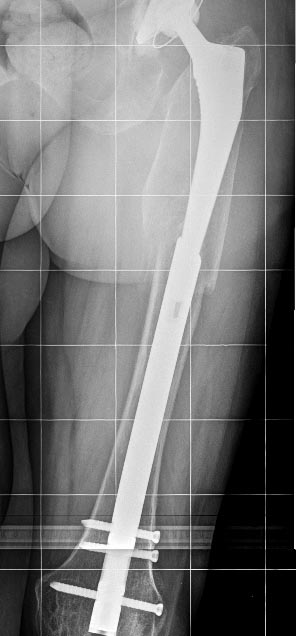

Надежность, если все правильно сделано, как минимум достаточная для любых нагрузок. Не понял насчет "был бы тех же размеров" - это и есть оскольчатый перелом, вот снимок до операции. Никаких верхних доступов, все закрыто. Принципы АО - вещь переменная, в конце 2013 г. издана аошная книжка про перипротезные переломы, там уже есть про эту методику. Цемент иногда действительно приходится удалять, но мы уже в 3 случаях смогли сделать без обнажения конца ножки, вытаскивали кусочки цемента через доступ для гвоздя. Не "ревизия ad oculus" подтверждает верность тактики, а результат. Представлен хороший непосредственный результат, будем надеяться, в дальнейшем он сохранится. А тактика верная - не обязательно одна. Могут быть и три првильных.

в этом случае перелом перипротезный на уровне эндопротеза с нестабильностю ножки. Это требует замены ножки. ПЛАСТИНА в любом случае требует большей инвазии. Здесь я за ножку вагнера.

Вот и было сделано нечто типа длинной ножки. Только закрыто и с запиранием.

Предлагаю вернуться к первоначальному снимку.

В смысле если посмотреть на первоначальный снимок - я бы не рискнул оперировать закрыто, без тщательного удаления цемента и фиксации лишь пятой дистальной части ножки в установленном через коленный сустав гвозде.

Михаил., без нашего опыта последних лет, может, и я бы не рискнул. С коленным суставом проблем не возникает. "доказательная база критериев определения" - просто прекрасно, запишу. Стабильность после сколачивания уже в десятках случаев эмпирически проверена. И "при нахождении линии" все хорошо. А после сращения можно сделать планово ревизию, и поставить первичный компонент.

Снимки красивые, но "люди ходят не на снимках, люди ходят на ногах". Поэтому не лишними были бы подобности типа возраста пациента, его уровня активности, хода операции (длительность, кровопотеря), ну и всякие другие небезинтересные вещи.

Не являюсь спецом по перипротезным переломам, но у нас как правило или остеосинтез или ревизионная ножка - что послужило здесь поводом сочетать оба метода?

"Операция выполнялась в соответствии со всеми принципами АО" - судя по количеству серкляжей вы с этой фразой немного погорячились. Кстати тоже: пластина позволяет вводить винты спереди и сзади от ножки протеза - почему предпочли не винты, а проволоку?